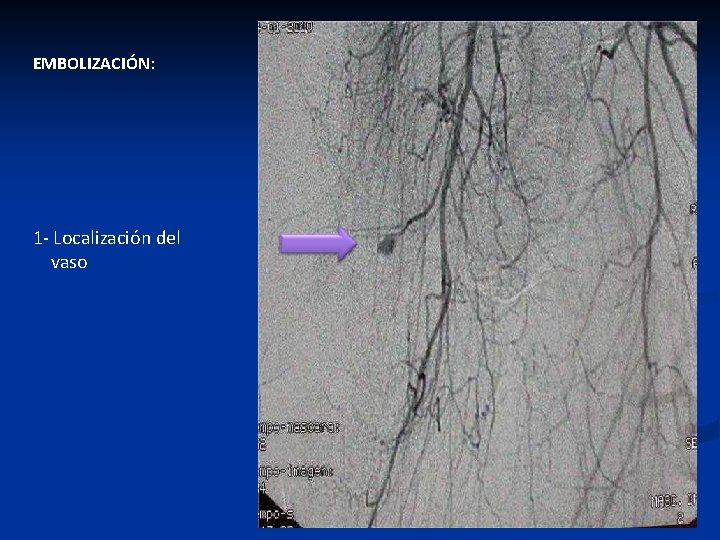

EMBOLIZACIÓN: 1 - Localización del vaso